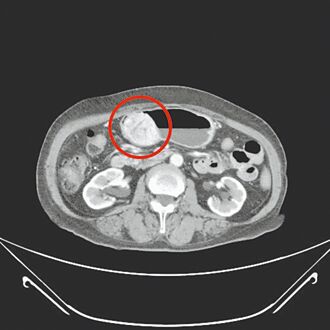

苗栗一名81歲老婦,因持續數月有腹痛及消化不良症狀,而在家人陪同下到衛福部苗栗醫院肝膽腸胃科就醫。經醫師檢查發現其胃部罹患罕見的胃腸道基質瘤(GIST),且腫瘤直徑竟已達24公分。經部苗消化外科醫療團隊縝密安排下順利完成手術,成功切除腫瘤,為她的健康帶來了希望。

一名七旬婦人3年前發現胃黏膜下有顆2公分的腫瘤,疑似胃腸道基質瘤,持續門診追蹤,近期發現腫瘤逐漸長大,2個月前上腹部悶痛、頭暈合併血便症狀,就醫檢查發現腫瘤已接近6公分,且膽囊被結石塞滿,沒有膽汁的空間,決定進行部分胃切除及膽囊切除手術。

南韓團體INFINITE的32歲成員南優賢(南優鉉)近來受訪時透露,於今年發現罹患胃腸道基質瘤(GIST),並在4月底接受10多小時的開腹手術,術後歷經相當艱辛的康復過程。醫師指出,胃腸道基質瘤是好發在胃腸道的惡性腫瘤,為僅次於大腸癌、胃癌的消化道惡性腫瘤,卻很少被人認識。由於症狀不明顯,近半患者幾乎沒有症狀,有症狀者大多是因腫瘤已大到一個程度,若是晚期已轉移不能切除者,平均存活率僅約1年。